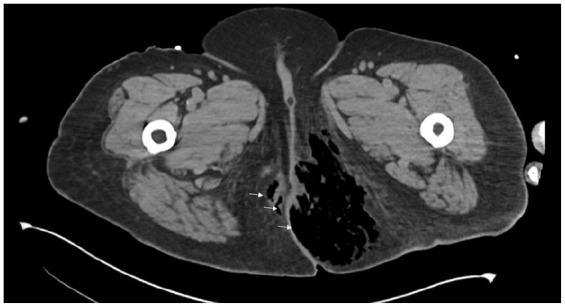

高血糖危机,包括糖尿病酮症酸中毒(DKA)和高血糖高渗状态(HHS),显著影响临床结果并造成沉重的经济负担。在不断增加的娱乐性药物滥用中,可卡因已成为最常被滥用的物质。然而,人们对可卡因使用与高血糖危机之间的关系了解有限。我们回顾性报告了4例可卡因滥用与DKA/HHS之间的关系。在病例1中,1型糖尿病(T1DM)患者表现为精神状态改变和DKA和HHS合并,其中可卡因使用导致错过胰岛素剂量,导致危机。病例2为同一例患者,后来因空洞性肺炎和败血症发展为DKA,需要机械通气、血管加压药和肾脏替代治疗。可卡因吸入导致肺部损伤,引发DKA。病例3涉及一名2型糖尿病(T2DM)患者,他静脉滥用可卡因,导致DKA-HHS和坏死性筋膜炎,需要紧急手术。病例4是一名肥胖、胰岛素抵抗和2型糖尿病患者,服用口服药物,可卡因可能加剧胰岛素抵抗并引发DKA。在所有4例病例中,治疗重点是积极补液、胰岛素输注、电解质纠正和解决潜在原因。高血糖危机在12至24小时内得到解决。然而,控制可卡因相关并发症证明是困难的,导致高发病率和死亡率,包括因呼吸道问题导致的精神状态改变、肾衰竭、横纹肌溶解和可能导致感染性休克或死亡的感染。在病例4中,可卡因使用显著加重了胰岛素抵抗和2型糖尿病,导致DKA。综上所述,可卡因滥用有多重影响,可以通过导致胰岛素剂量不足、脱水、感染和胰岛素抵抗的慢性恶化而引发高血糖危机。可卡因滥用可通过多种机制触发和/或加重高血糖危象,如对心肺和肾脏系统的损害、社会心理变化、免疫力减弱和感染,以及激素和代谢的改变(图3)。我们建议将药物滥用问题纳入常规的患者病史评估和进行毒理学筛查,特别是对经常入院的DKA/HHS患者。此外,我们分享我们在管理这一特定患者群体方面的专业知识。

Hyperglycemic crises, including diabetic ketoacidosis (DKA) and hyperglycemic hyperosmolar state (HHS), significantly affect clinical outcomes and impose a heavy economic burden. Among the steadily increased recreational drug abuse, cocaine has become the most frequently misused substance. However, there is limited understanding of the relationship between cocaine use and hyperglycemic crises. We report 4 cases retrospectively to examine the relationship between cocaine abuse and DKA/HHS. In Case 1, a patient with Type 1 diabetes mellitus (T1DM) presented with altered mental status and a combination of DKA and HHS, where cocaine use led to missed insulin doses, resulting in the crisis. Case 2 involved the same patient who later developed DKA due to cavitary pneumonia and sepsis, requiring mechanical ventilation, vasopressors, and renal replacement therapy. Cocaine inhalation caused pulmonary damage that triggered DKA. Case 3 involved a patient with Type 2 diabetes mellitus (T2DM) who abused cocaine intravenously, leading to DKA-HHS and necrotizing fasciitis that required emergency surgery. Case 4 was a patient with obesity, insulin resistance, and T2DM on oral medications, where cocaine likely exacerbated insulin resistance and triggered DKA. In all 4 cases, treatment focused on aggressive rehydration, insulin infusion, electrolyte correction, and addressing underlying causes. The hyperglycemic crises resolved within 12 to 24 hours. However, managing cocaine-related complications proved difficult, leading to high morbidity and mortality rates, including altered mental status with airway issues, kidney failure, rhabdomyolysis, and infections that could result in septic shock or death. In Case 4, cocaine use significantly worsened insulin resistance and T2DM, contributing to DKA. In conclusion, cocaine abuse has multiple effects and can act as an unusual trigger for hyperglycemic crises by causing missed insulin doses, dehydration, infections, and chronic worsening of insulin resistance. Cocaine abuse can trigger and/or worsen hyperglycemic crises through various mechanisms, such as damage to the cardiopulmonary and renal systems, psychosocial changes, weakened immunity and infections, and alterations in hormones and metabolism (Figure 3). We suggest incorporating questions about substance abuse into routine patient history assessment and performing toxicology screenings, particularly for individuals who have frequent admissions for DKA/HHS. Additionally, we share our expertise in managing this specific group of patients.